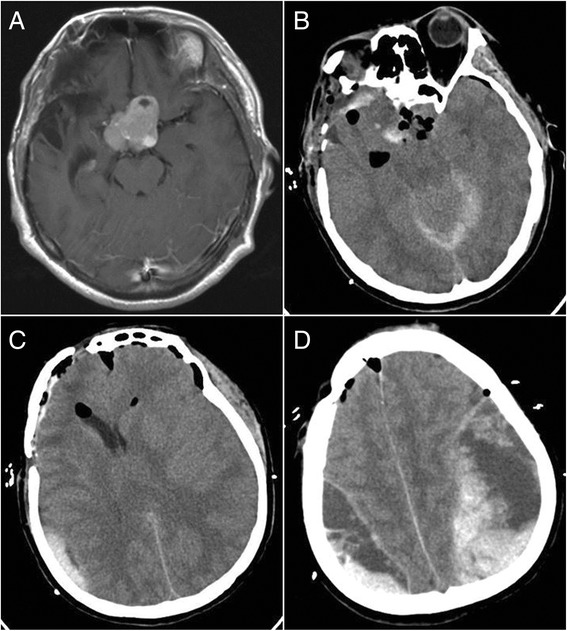

Fig. 4.

Bilateral remote hemorrhage in case 11. a Preoperative-enhanced MRI revealed a sellar tumor. b CT showed the tumor resection. c, d CT revealed epidural hematomas at the tops of bilateral sides